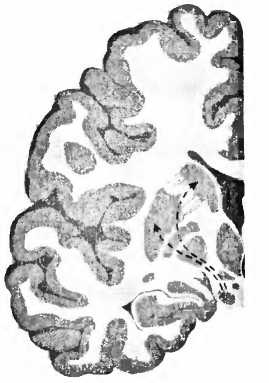

Для болезни Паркинсона характерно отмирание дофаминовых клеток в черной субстанции (substantia nigra) мозгового ствола (рис. 23). При вскрытии эта область мозга из-за пигментации клеток, вырабатывающих дофамин, выглядит как проходящая через мозговую ткань черная лента. И если эти клетки мертвы, их сразу же видно, как, например, при болезни Паркинсона. Тогда клетки не могут больше иннервировать полосатое тело (стриатум), моторную область в центре мозга, то есть снабжать ее нервными волокнами и управлять ею. Из-за недостатка в стриатуме дофамина возникают типичные для этой болезни расстройства движения. Что может быть логичнее, чем лечить эту болезнь заменой умерших клеток? В1987 году в ведущем профессиональном журнале The New England Journal of Medicine[89] появилась статья мексиканского врача Мадрасо, в которой он сообщал о поразительном улучшении у больного паркинсонизмом после аутотрансплантации ткани дофаминсодержащих клеток надпочечников в хвостатое ядро (nucleus caudatus, рис. 23). В ближайшие два года сообщение привело к лавине из 200 подобных трансплантаций. Но операция оказалась неэффективной, и в течение двух лет после нее 20 % пациентов умерли. Исследование мозга умерших показало, что трансплантированная из надпочечников ткань в мозге не прижилась. В стриатуме были видны только шрамы. Многообещающие результаты Мадрасо были основаны, вероятно, на непрофессионально проведенных исследованиях в сочетании с эффектом плацебо (см. XVII.4).

NCSN норма

болезнь Паркинсона

Рис. 23. При болезни Паркинсона пигментированные черным клетки, производящие дофамин в черной субстанции (SN), умирают и уже больше не могут управлять моторной областью — полосатым телом стриатумом (Р — putamen, скорлупа; NC — nucleus caudatus, хвостатое ядро).